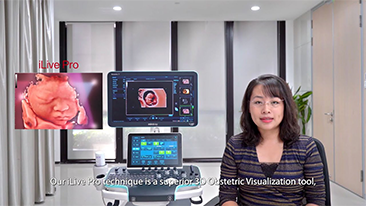

L'optimisation des flux de travail en gynÊcologie et obstÊtrique est indispensable pour traiter les volumes importants de patientes se prÊsentant pour des dÊpistages. Par exemple, les malformations du système nerveux central (SNC) font partie des anomalies congÊnitales les plus frÊquentes. Compte tenu des diffÊrentes conditions dans lesquelles sont rÊalisÊes les Êchographies, par exemple lorsque le f?tus est mal positionnÊ, il est particulièrement difficile de visualiser le plan transcÊrÊbelleux sur les Êchographies 2D. L'automatisation de la dÊtection et de la prise de mesures peut donc grandement amÊliorer l'efficacitÊ de l'imagerie.